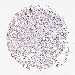

CANCER BREAST CANCER Show tissue menu

BRCA TCGA BRCA VALIDATION PROTEIN EXPRESSION

Breast cancer

Human cancer